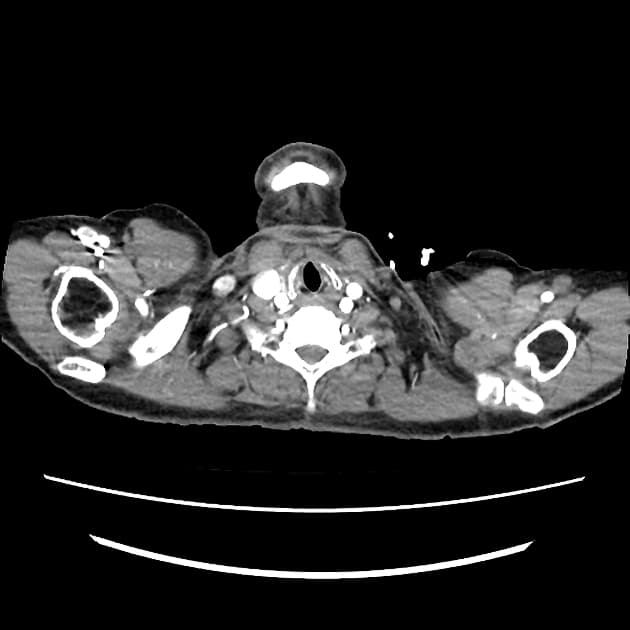

- Thấy vạt bóc tách (flap) trong động mạch chủ (aorta), xuất phát ở đoạn động mạch chủ lên (ascending aorta) ngay phía dưới gốc động mạch chủ (aortic root), xoắn dọc theo toàn bộ động mạch chủ (aorta), tạo thành buồng giả (false lumen) lớn nằm chủ yếu phía sau và chèn ép buồng thật (true lumen), buồng thật có hình bầu dục trên mặt cắt ngang.

- Vạt bóc tách lan xuống đến các động mạch chậu chung (common iliac arteries) ở đoạn trên vùng khảo sát.

- Thân tạng (coeliac trunk), động mạch mạc treo tràng trên (mesenteric artery) và cả hai động mạch thận (renal arteries) đều xuất phát từ buồng thật (true lumen); các động mạch thận (renal arteries) có vẻ tản rộng do động mạch chủ (aorta) giãn và dịch chuyển.